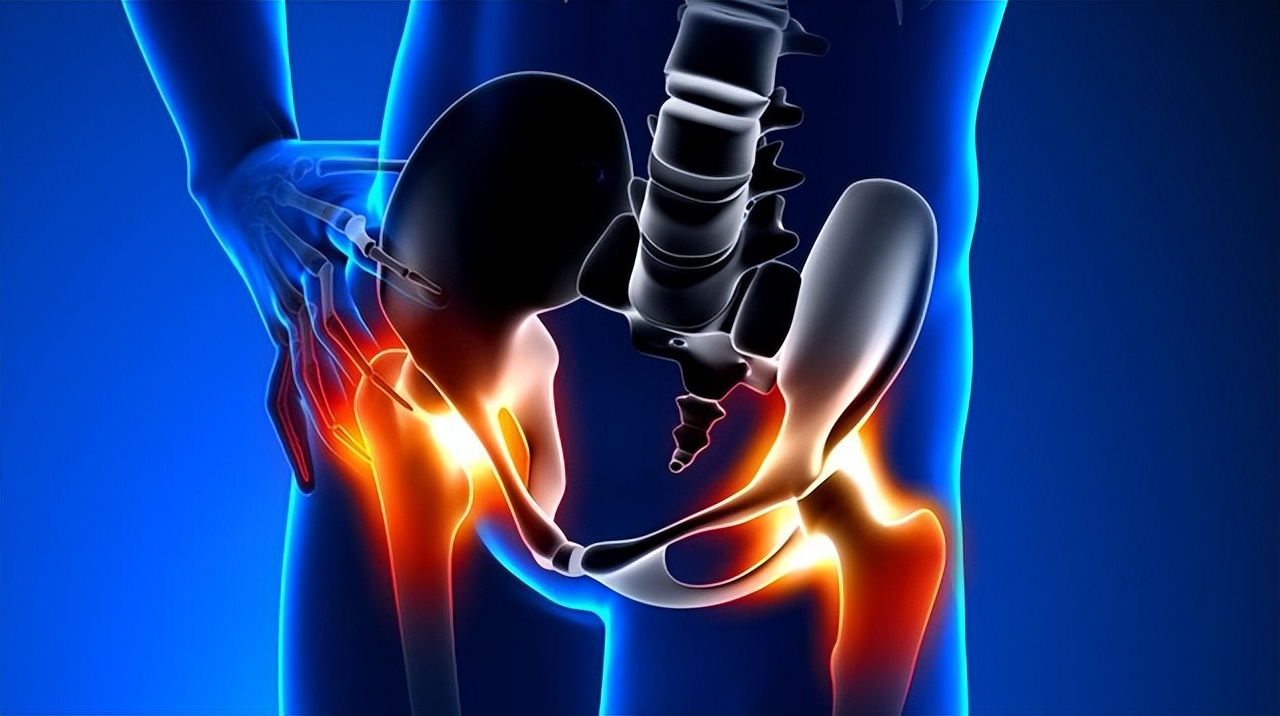

股骨头坏死又称为股骨头缺血性坏死或股骨头无菌性坏死,指股骨头血供受损或中断,导致骨髓成分及骨细胞死亡及随后的组织修复,继而导致股骨头结构改变及塌陷,引起患者髋关节疼痛及功能障碍的疾病,是造成青壮年髋关节残疾的常见疾病之一。

1、疼痛:多发生于股骨头中央部位,即腹股沟部位,疼痛有时会局限腹股沟部位,也发生于膝关节和髋关节周围,有些患者疼痛沿大腿内侧放射到膝关节,可能会因治疗膝关节痛而忽略股骨头坏死,导致误诊,延误治疗。临床一定要进行科学分析和准确检查,才能明确是否由股骨头坏死引起疼痛;